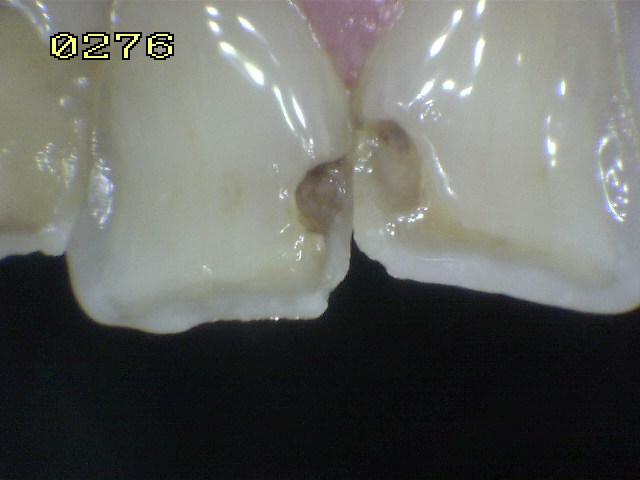

Código 5